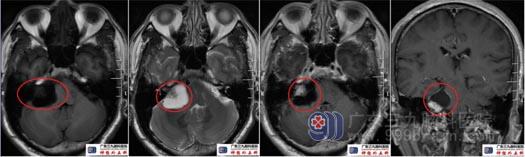

术前头颅MRI示右侧桥小脑角区有一大小约35mm×26mm×28mm的团块状囊实性占位性病变,实性部分呈不均等长T1、等长T2信号、Flair序列呈等稍高混杂信号,局部凸入右侧内听道,囊性部分呈长T1、长T2、Flair序列呈稍低信号,增强扫描后实性部分及囊壁可见明显强化,邻近脑干-右侧桥臂-小脑半球明显受压。考虑为囊性听神经鞘瘤。